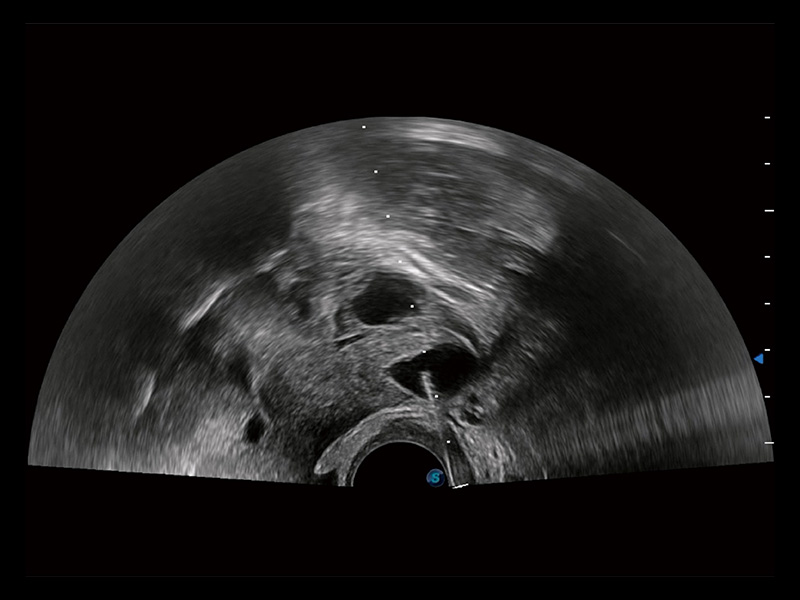

超声引导下胚胎移植

宫外孕血流